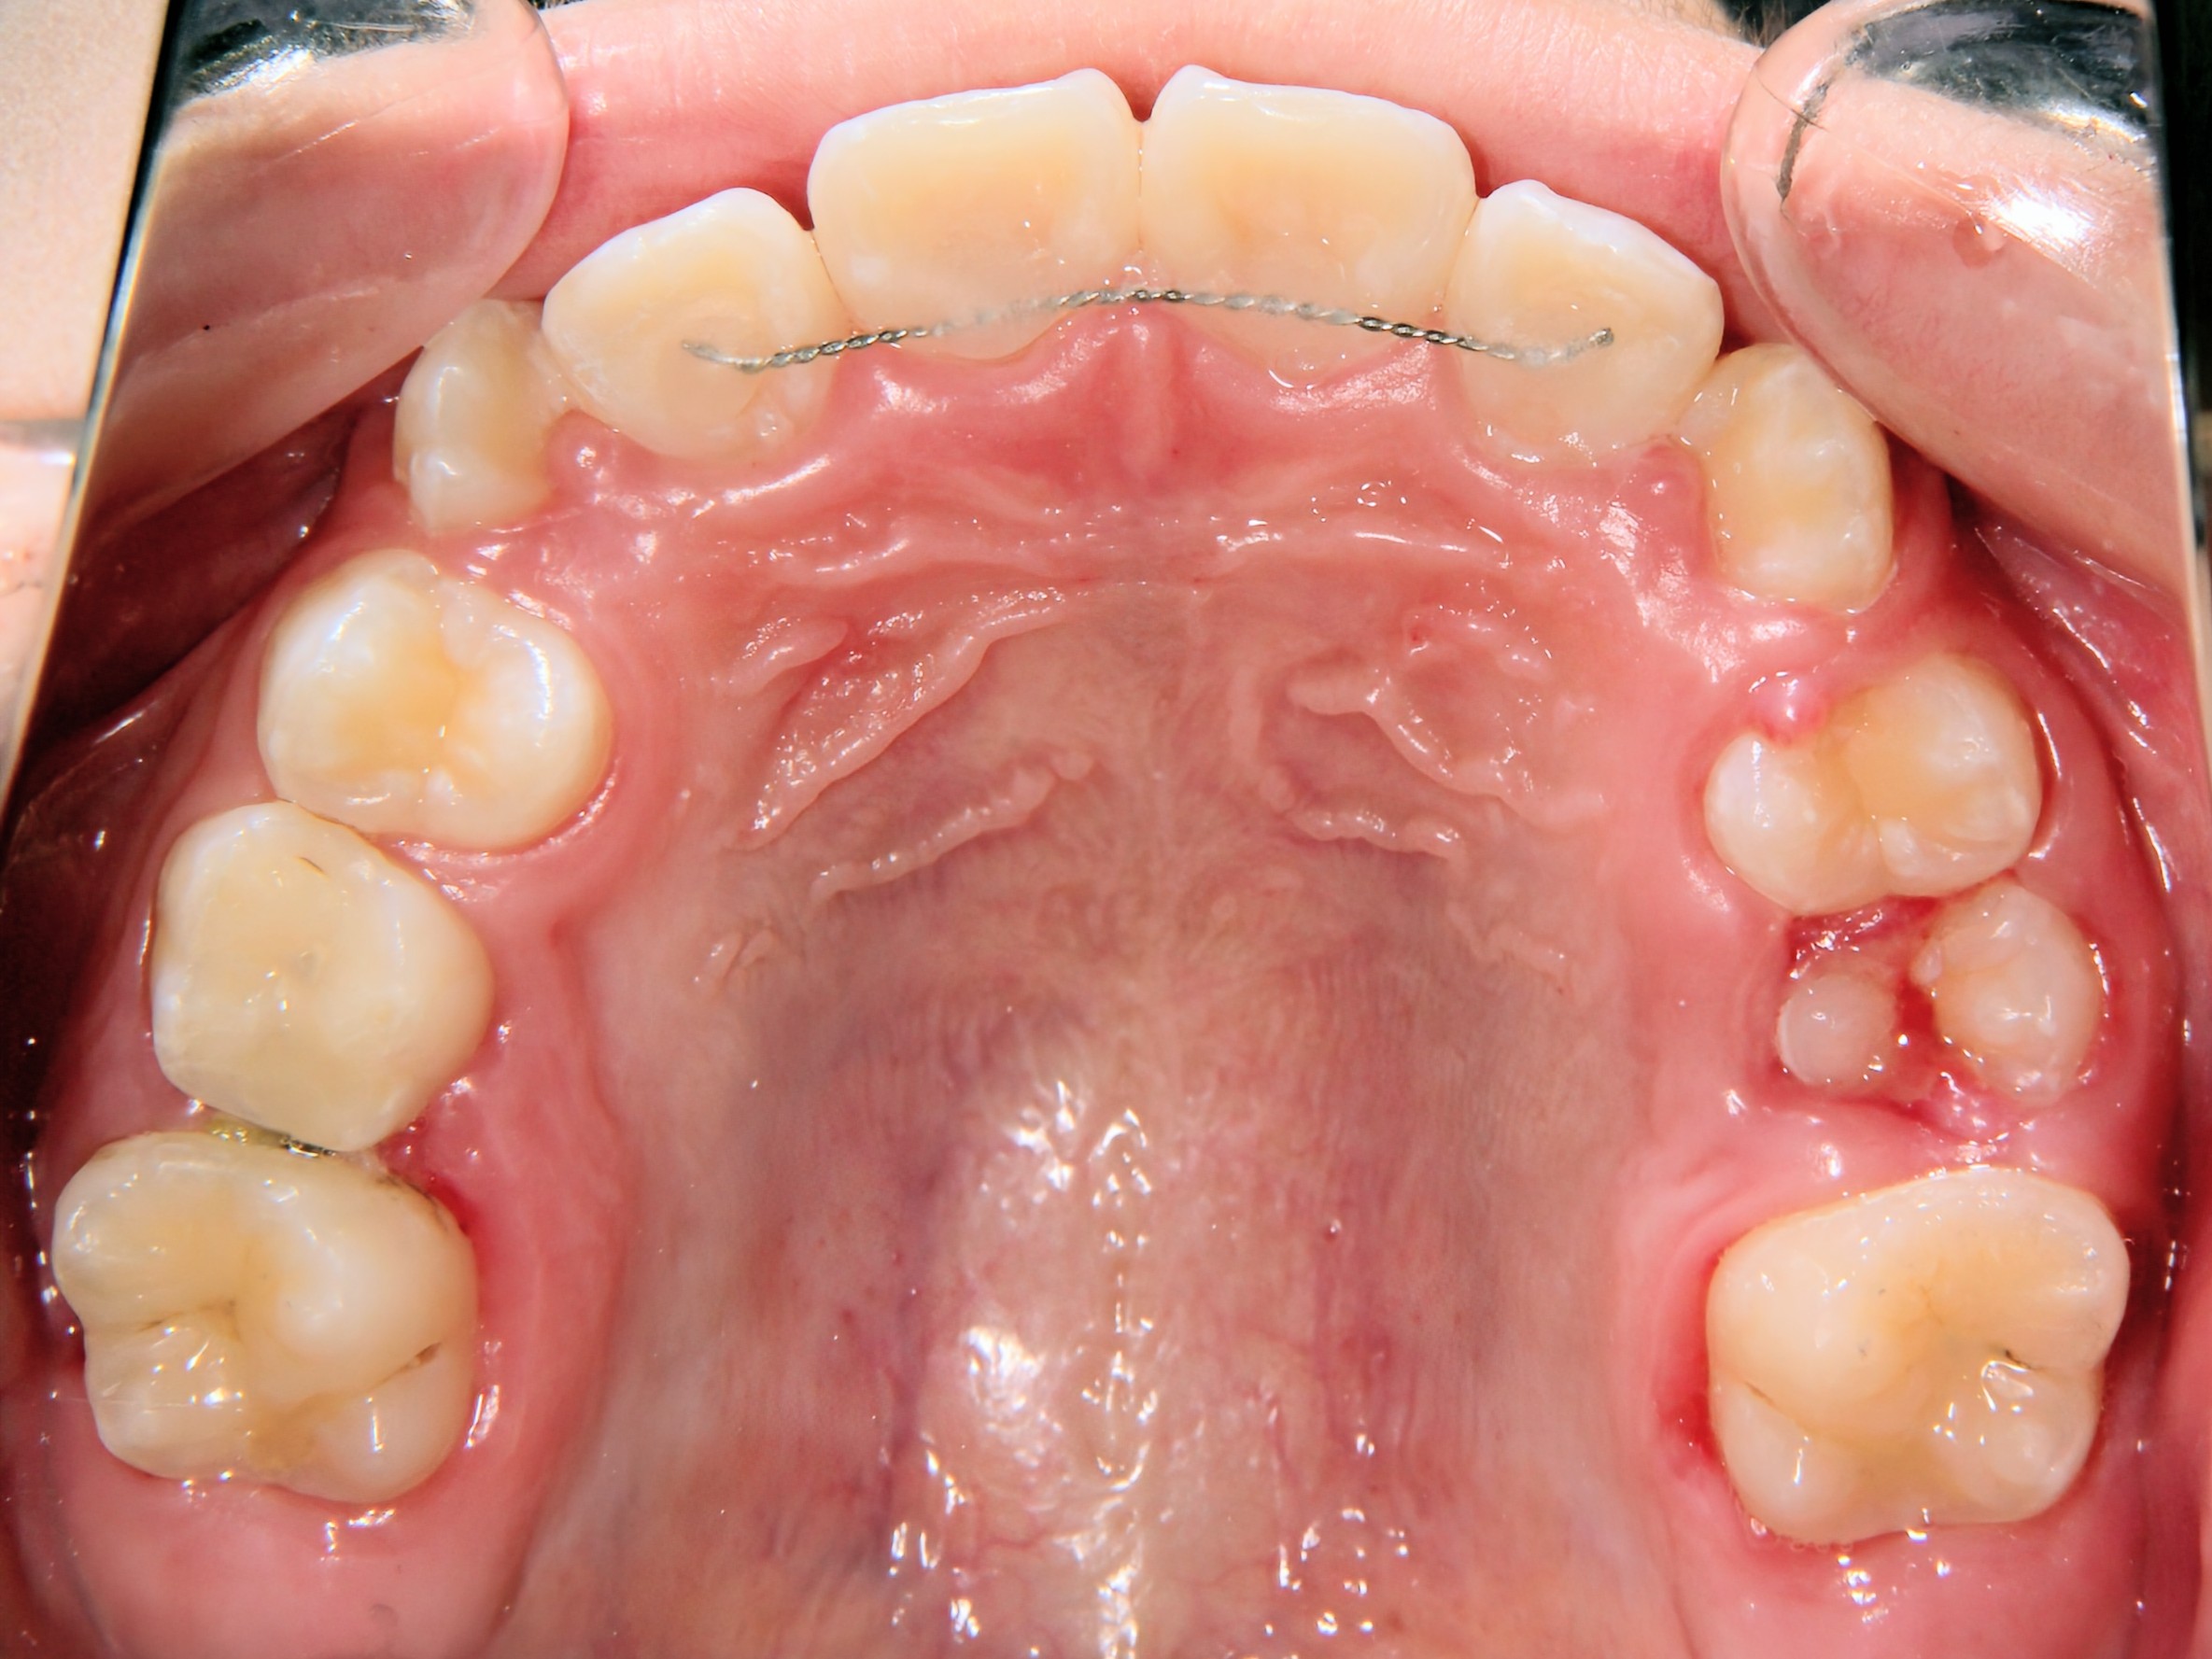

第1期治療開始時

口腔内写真

年齢

9歳 男性

主訴(患者様のお悩み)

歯のデコボコを治したい

診断

上顎前歯部叢生(上の前歯のデコボコ)

上下顎側切歯クロスバイト(部分受け口)

上顎狭窄歯列(上のあごが小さめ)

歯冠幅径大(歯が大きめ)

治療方針

上顎緩徐拡大(上あごを拡大)

上の前歯部のみワイヤー矯正

使用装置

緩徐拡大装置(クワドヘリックス)

前歯部ブラケット

治療期間の目安:約半年~1年(保定期間を除いた期間)